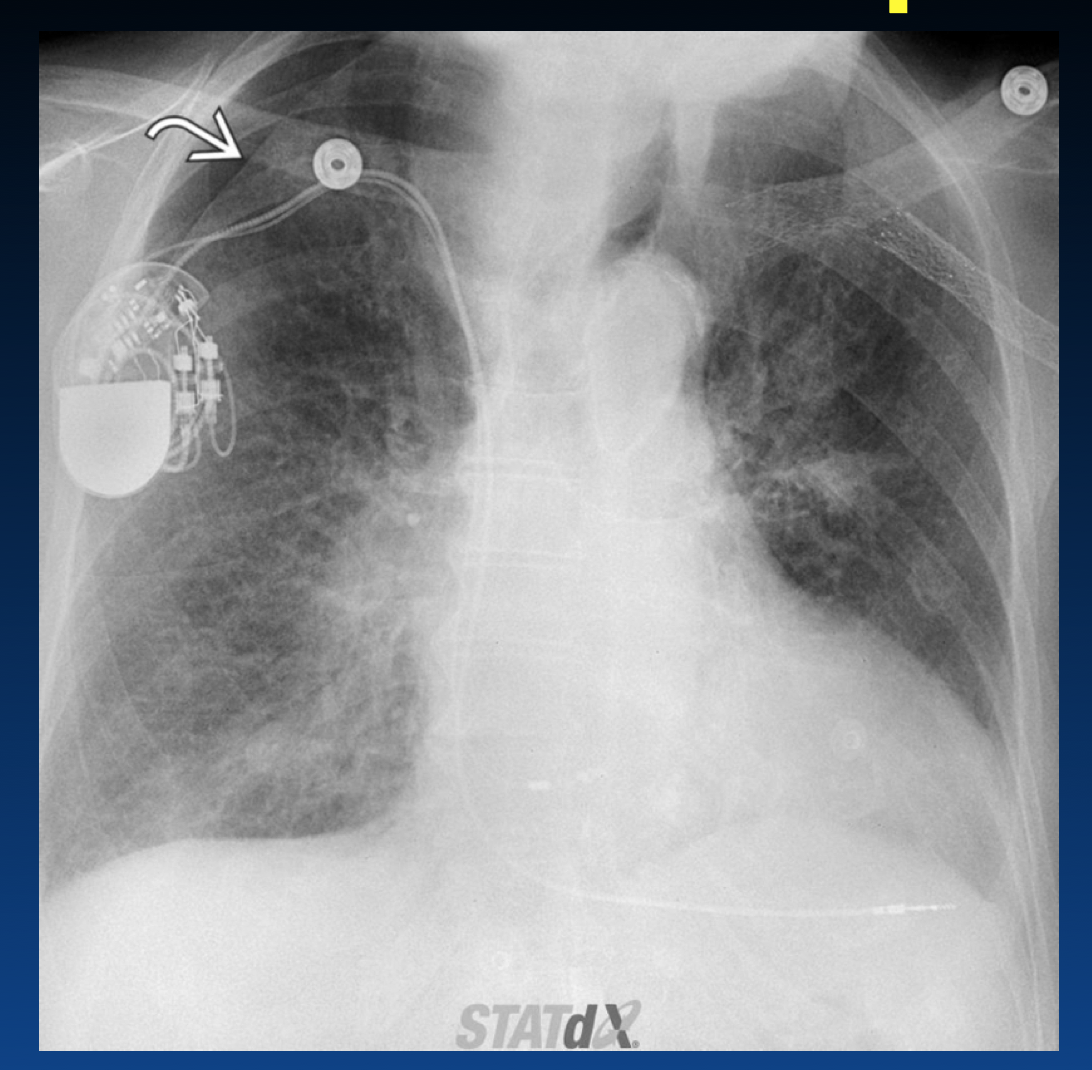

What kind of pacemaker is described?

What device is described?

What kind of pacemaker is this?

What device is shown?

What is wrong with this?

What kind of pacemaker is shown?